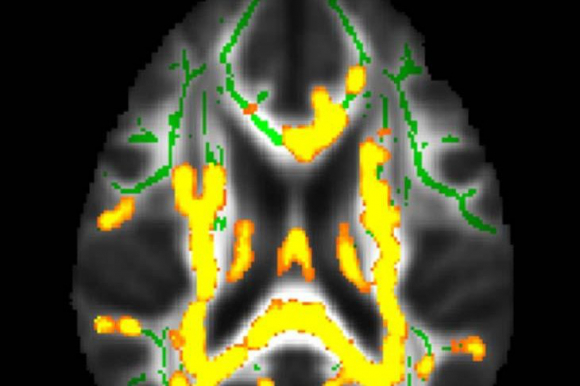

Hình ảnh cho thấy tình trạng viêm thần kinh gia tăng (màu vàng). Điều này có liên quan đến lượng mỡ ẩn (mỡ nội tạng) - Ảnh: RSNA

Ngoài ra, 32 người được chụp PET CT (loại chẩn đoán hình ảnh đặc biệt giúp tiết lộ cách các mô và cơ quan hoạt động) để kiểm tra bệnh Alzheimer.